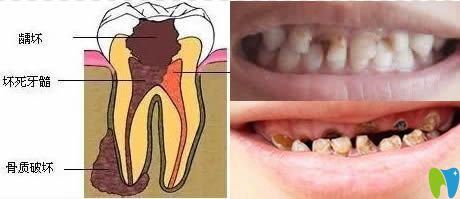

我們通過下圖來看看齲齒發(fā)展速度有多快?

齲齒發(fā)展過程圖解

1、先是齲壞于牙釉質(zhì)層;2、發(fā)展到牙本質(zhì),這時(shí)已對(duì)冷熱刺激感到敏感;3、牙髓炎階段,開始自發(fā)陣痛;4、由牙髓感染導(dǎo)致根尖發(fā)炎疼痛,面部腫脹;5、牙冠破壞,根尖病變,牙頜骨質(zhì)開始遭到破壞。